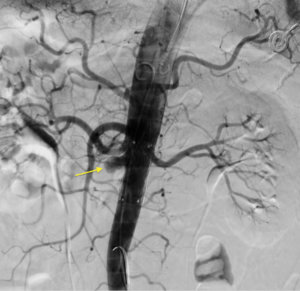

Под местной анестезией выполнено четыре пункции сосудов рук и ног (плечевые и бедренные артерии справа и слева) и выполнено уникальное эндоваскулярное протезирование брюшного отдела аорты стент-графтом от уровня почечных артерий и самих почечных артерий, таким образом исключив из кровотока патологический процесс – артериовенозное сообщение.

По данным контрольной ангиографии непосредственно после оперативного вмешательства: адекватное позиционирование стент-графтов, без признаков диссекций, нарушения целостности артериальных сосудов. Почечные артерии и верхняя брыжеечная артерия проходимы, почечная вена визуально уменьшилась до нормальных размеров.